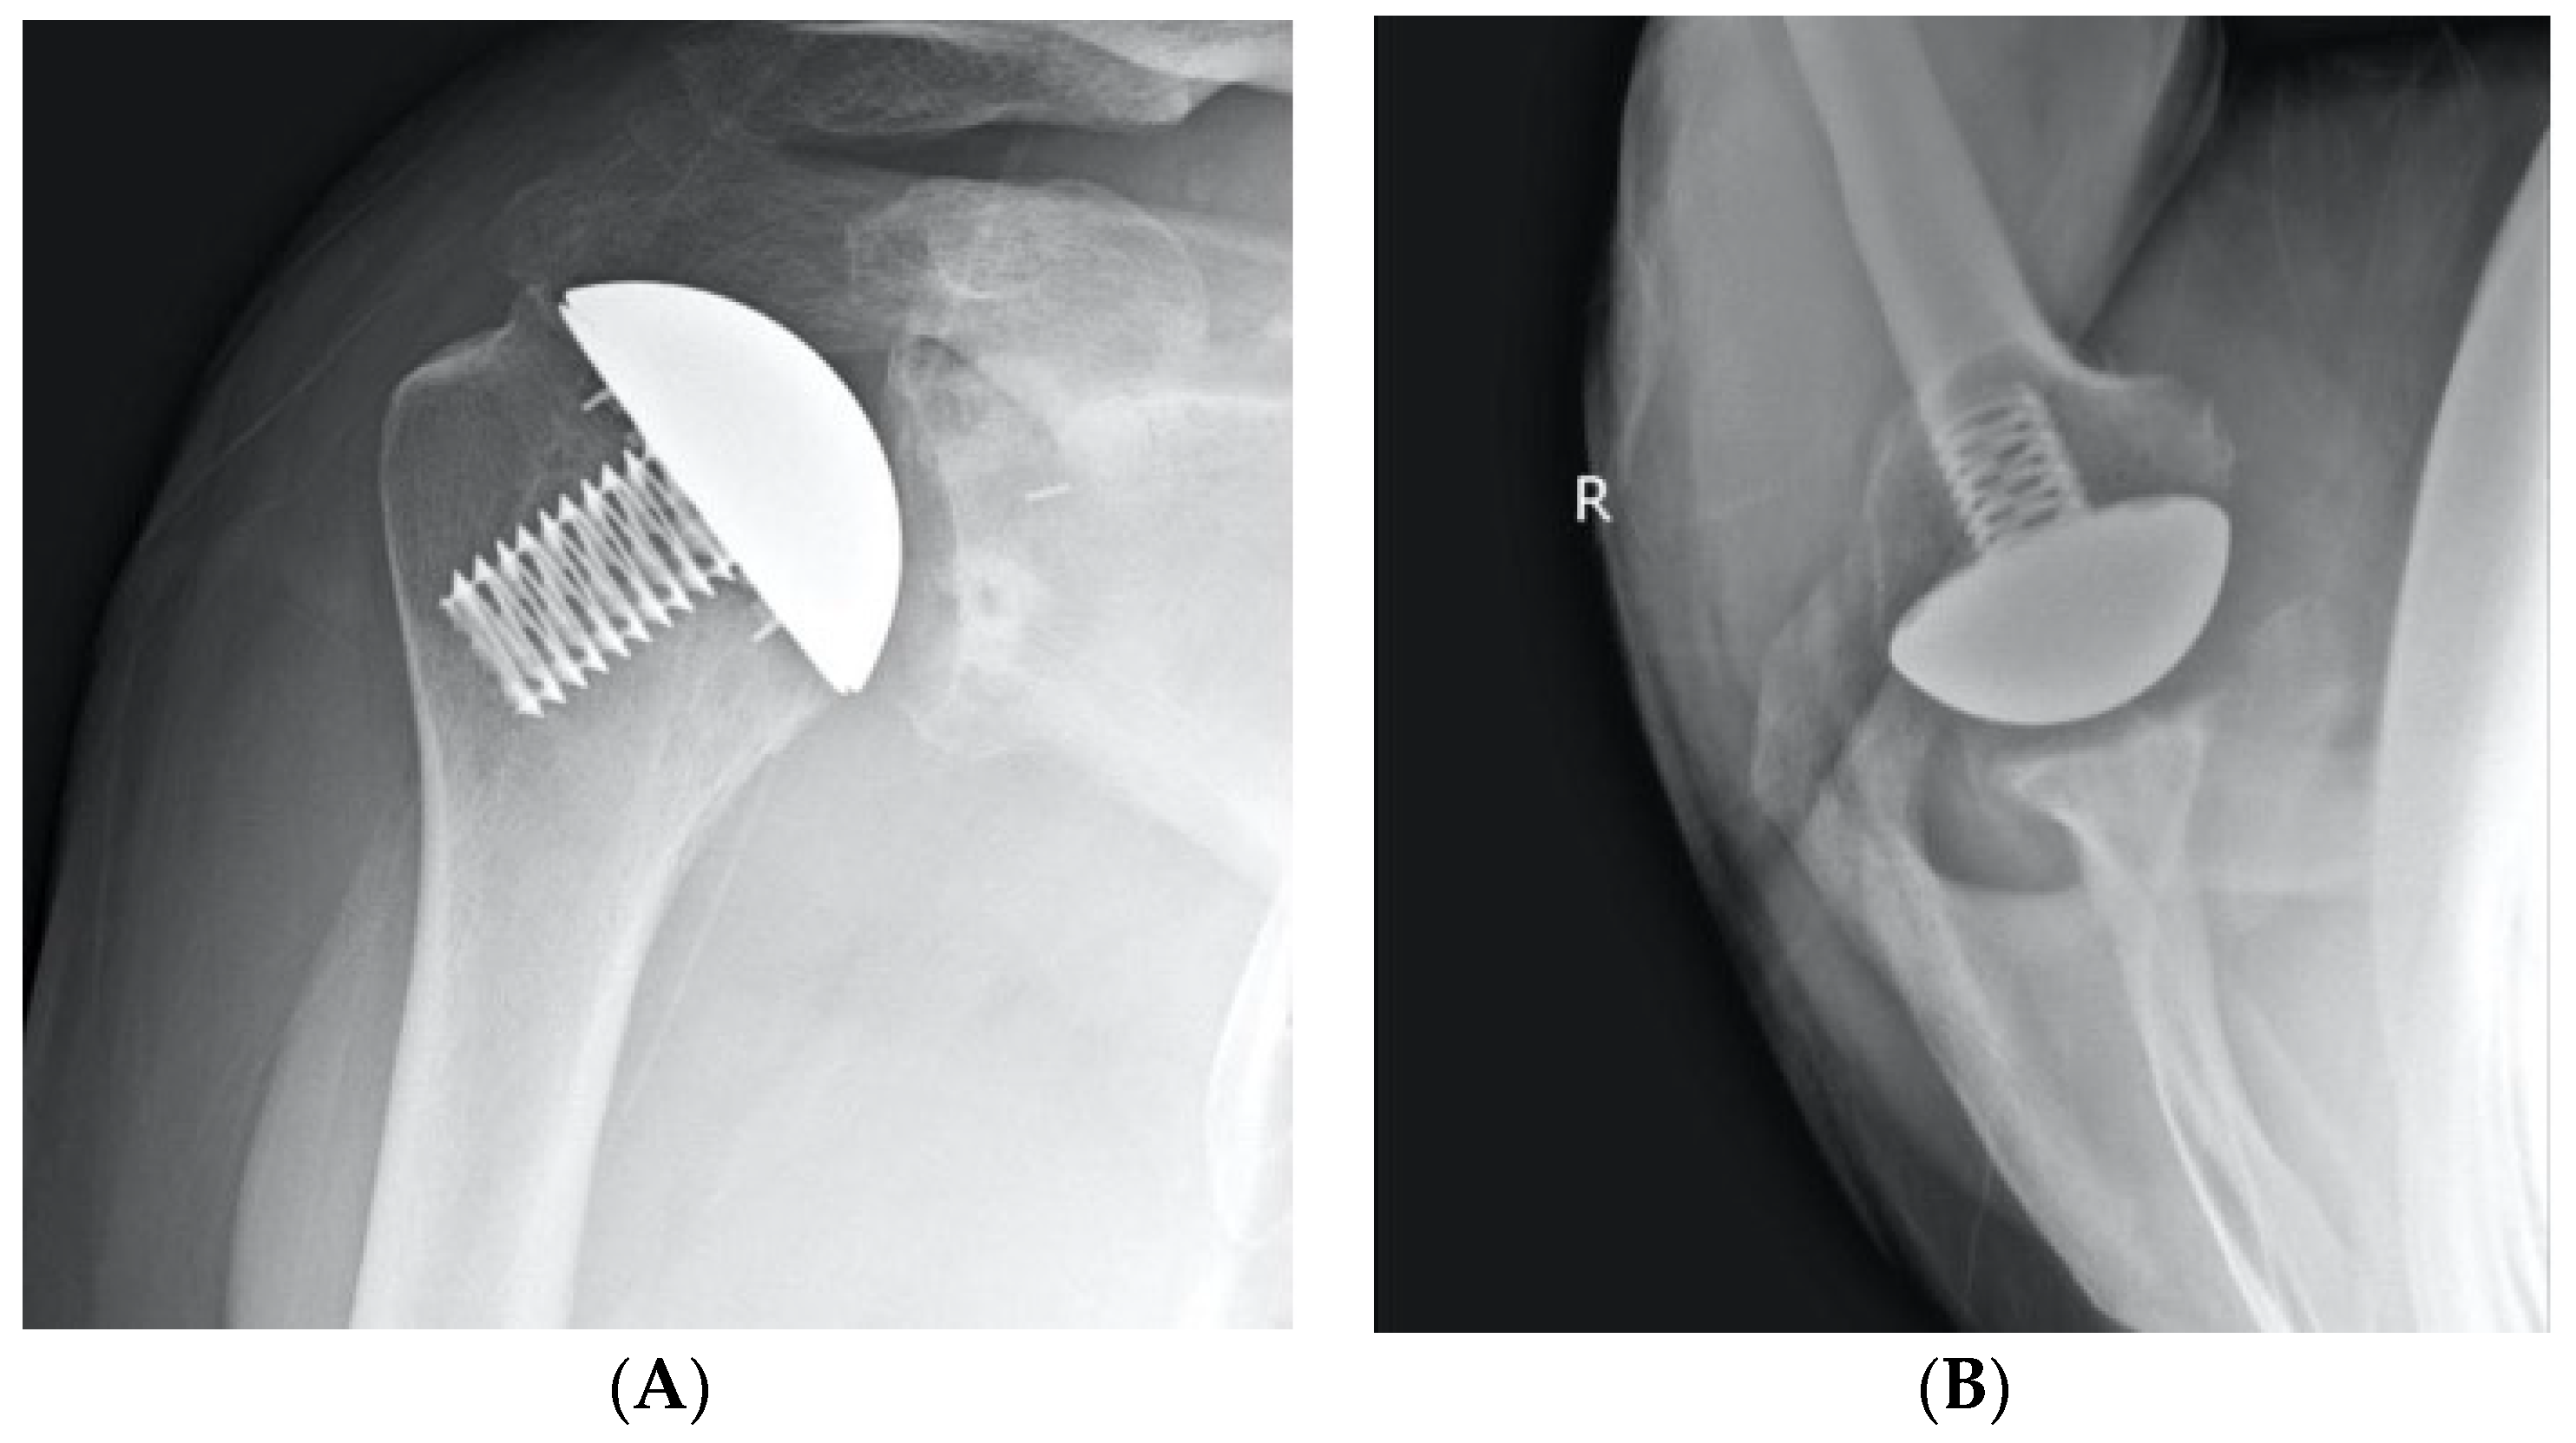

2.2. Surgical Technique

2.3. Radiographic Evaluation

- Small, K.M.; Siegel, E.J.; Miller, L.R.; Higgins, L.D. Imaging Characteristics of Lesser Tuberosity Osteotomy after Total Shoulder Replacement: A Study of 220 Patients. J. Shoulder Elb. Surg. 2014, 23, 1318–1326. [Google Scholar] [CrossRef]